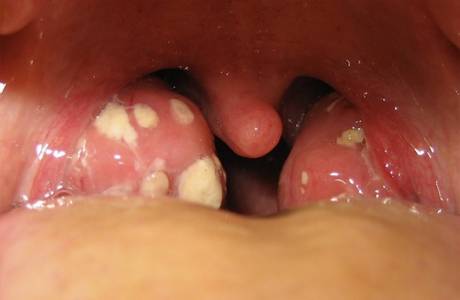

Jest to patologiczny proces zapalenia migdałków, w którym gardło jest bardzo obolałe, a obecność ropnych złogów na szczelinach elokwentnie opisuje charakterystyczną dolegliwość. Brak terapii prowadzi nie tylko do ostrej utraty wagi pacjenta, ale także do przewlekłego zapalenia migdałków z nawrotami. Możesz wyleczyć ropny ból gardła metodami zachowawczymi, jeśli specjalista wybierze odpowiednie leczenie.

Jeśli nie wyleczysz ropnego zapalenia migdałków w odpowiednim czasie, na migdałkach tworzą się niebezpieczne ropnie. Zdjęcia takich zdjęć klinicznych są szokujące, dlatego zaleca się zwrócenie uwagi na pierwsze objawy choroby zakaźnej. W przypadku braku terminowych kompleksowych środków w celu wyeliminowania ropnego zapalenia migdałków, inne potencjalne powikłania przedstawiono poniżej: